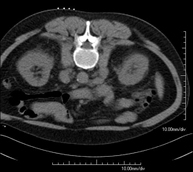

- Abdomen y pelvis- TC Abdomen Prueba diagnóstica que consiste en obtener imágenes del abdomen de alta definición anatómica (hígado, vesícula biliar, vía biliar, páncreas, bazo, estómago, intestinos, riñones, estructuras vasculares, vejiga, útero y ovarios, etc.) mediante el empleo de un equipo de TC (Tomografía Computarizada). Dichas imágenes se estudian posteriormente en una estación de trabajo que permite reconstrucciones bidimensionales en diferentes planos del espacio, y también reconstrucciones 3D (volumétricas). La mayoría de estudios requieren el empleo de contraste yodado para mejorar la definición de las imágenes. Prueba diagnóstica que consiste en obtener imágenes del abdomen de alta definición anatómica (hígado, vesícula biliar, vía biliar, páncreas, bazo, estómago, intestinos, riñones, estructuras vasculares, vejiga, útero y ovarios, etc.) mediante el empleo de un equipo de TC (Tomografía Computarizada). Dichas imágenes se estudian posteriormente en una estación de trabajo que permite reconstrucciones bidimensionales en diferentes planos del espacio, y también reconstrucciones 3D (volumétricas). La mayoría de estudios requieren el empleo de contraste yodado para mejorar la definición de las imágenes.

- TC Abdominopélvico Prueba diagnóstica que consiste en obtener imágenes bi y tridimensionales del abdomen y de la pelvis de alta definición anatómica (estructuras óseas, estructuras vasculares, hígado, páncreas, vesícula biliar, riñones, glándulas suprarrenales, bazo, intestino delgado y grueso, vejiga, útero y ovarios, próstata y vesículas seminales, uréteres, etc.) mediante el empleo de un equipo de TC (Tomografía Computarizada). La mayoría de estudios requieren el empleo de contraste yodado. Prueba diagnóstica que consiste en obtener imágenes bi y tridimensionales del abdomen y de la pelvis de alta definición anatómica (estructuras óseas, estructuras vasculares, hígado, páncreas, vesícula biliar, riñones, glándulas suprarrenales, bazo, intestino delgado y grueso, vejiga, útero y ovarios, próstata y vesículas seminales, uréteres, etc.) mediante el empleo de un equipo de TC (Tomografía Computarizada). La mayoría de estudios requieren el empleo de contraste yodado.